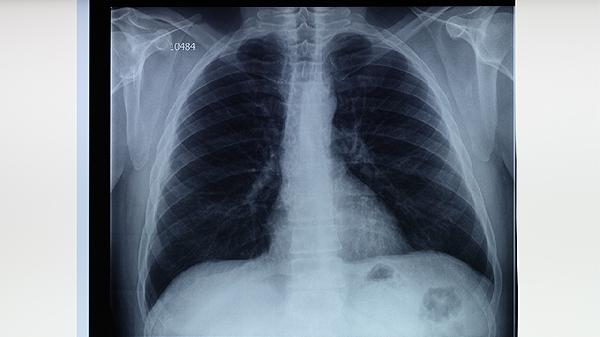

肺结核的治疗需遵循医生指导,坚持全程、规律服药,避免擅自停药或更改剂量。定期复查肺部CT和痰液检查,监测病情变化。保持良好的生活习惯,如充足睡眠、适度运动和心情愉悦,有助于加快康复进程。如出现药物副作用或病情加重,应及时就医调整治疗方案。